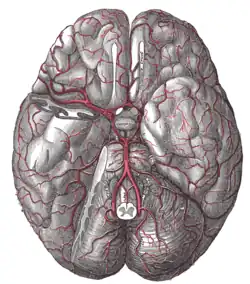

Pituitary and pineal glands The arteries of the base of the brain

The arteries of the base of the brain Mesal aspect of a brain sectioned in the median sagittal plane